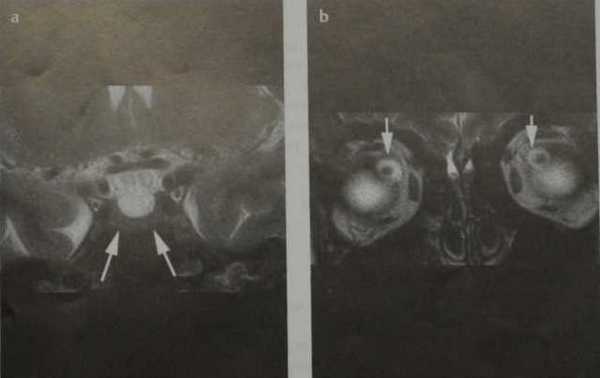

Псевдоопухоль головного мозга. МРТ, Т2-ВИ во фронтальной плоскости (а, b). Уплощенный гипофиз на дне турецкого седла (а; стрелки). Двустороннее расширение ликворных пространств вокруг зрительных нервов (b; стрелки).